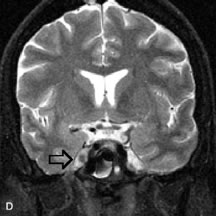

MRI and MRV are more sensitive than CT in revealing cavernous sinus thrombosis. Engorgement of the cavernous sinus, extraocular muscles, and ophthalmic veins is seen with hyperintensity of the thrombosed sinuses evident on all pulse sequences. The enlarged, thrombosed superior ophthalmic vein appears less hypointense than the normal contralateral ophthalmic vein, and hyperintensity within the lumen of the vessel may be seen on T1- and T2-weighted MR images.68

MRI is an excellent modality for demonstrating enlargement of the cavernous sinus and dilation of the superior ophthalmic vein in patients with high-flow carotid-cavernous fistulas (Fig. 14).37MRA may be helpful in the evaluation of the venous outflow pattern. The rapidly flowing blood in these vascular structures carries the excited protons out of the section before they can be imaged, resulting in their dark appearance.5 In low-flow dural arteriovenous malformations, MRA may help define the arterial feeding vessels.45

Fig. 14. Patient with Ehlers-Danlos syndrome who presented with abrupt onset of severe proptosis. A-C. Postcontrast fat-suppressed T1-weighted MR scans demonstrate marked proptosis and engorgement of the extraocular muscles and superior ophthalmic vein (arrows). D. T2-weighted scan through the cavernous sinus demonstrates enlargement and arterialized flow void within the right cavernous sinus (open arrow).